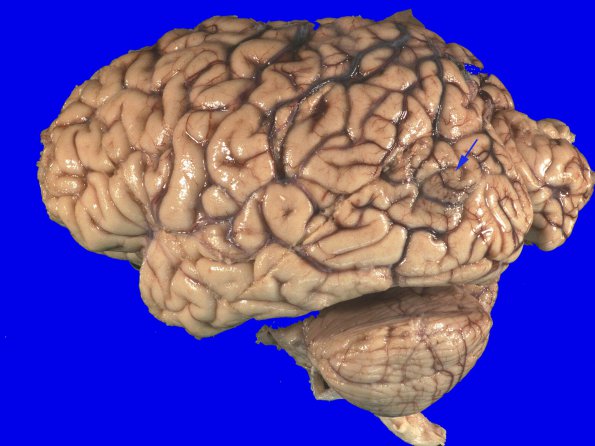

Case 18 ---- The patient was a 66 year old woman with a history of severe mitral regurgitation, congestive heart failure, hypertension, type 2 diabetes, colon cancer s/p resection in 2001, and coronary artery disease. She underwent two vessel CABG and mitral valve repair surgery in June 2012. After an initial window of uneventful recovery she developed renal and respiratory failure and required tracheostomy on 6/20. A head CT performed on 6/22 in response to the patient's altered mental status, showed subacute infarction in the left occipital lobe. Bradycardia was followed by asystole and she died on July 26th, approximately one week after her terminal decompensation. ---- 18A1The external surface shows a discolored focus (arrow) involving the left occipital lobe.